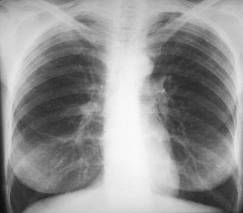

Cordul orizontalizat - se întâlneste la obezi. Axul longiudinal al cordului este orizontalizat, cordul este culcat pe diafragm si se desfasoara în sens transversal spre stânga.

INSUFICIENŢA AORTICĂ

- largirea pedicolului vascular prin dilatarea aortei ascendente si accentuarea importanta a butonului aortic

marirea arcului inferior stâng prin hipertrofia si dilatarea ventricolului stâng

adâncirea arcului mijlociu

La examenul radioscopic, se evidentiaza pulsatii ample la nivelul arcului inferior stâng, a aortei ascendente si butonului aortic.